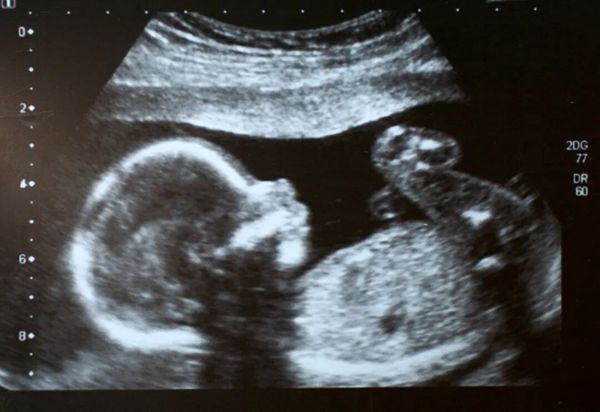

遵循中医“种子必先调经”的原则,在肾气充足、气血调和的基础上,肖婷医生适时助孕,帮助李女士成功自然妊娠。

李女士的调理-助孕经历也印证了中医“肾-天癸-冲任-胞宫”轴理论的科学性和实用性,通过分阶段辨证施治,实现了调经与助孕的双重目标。